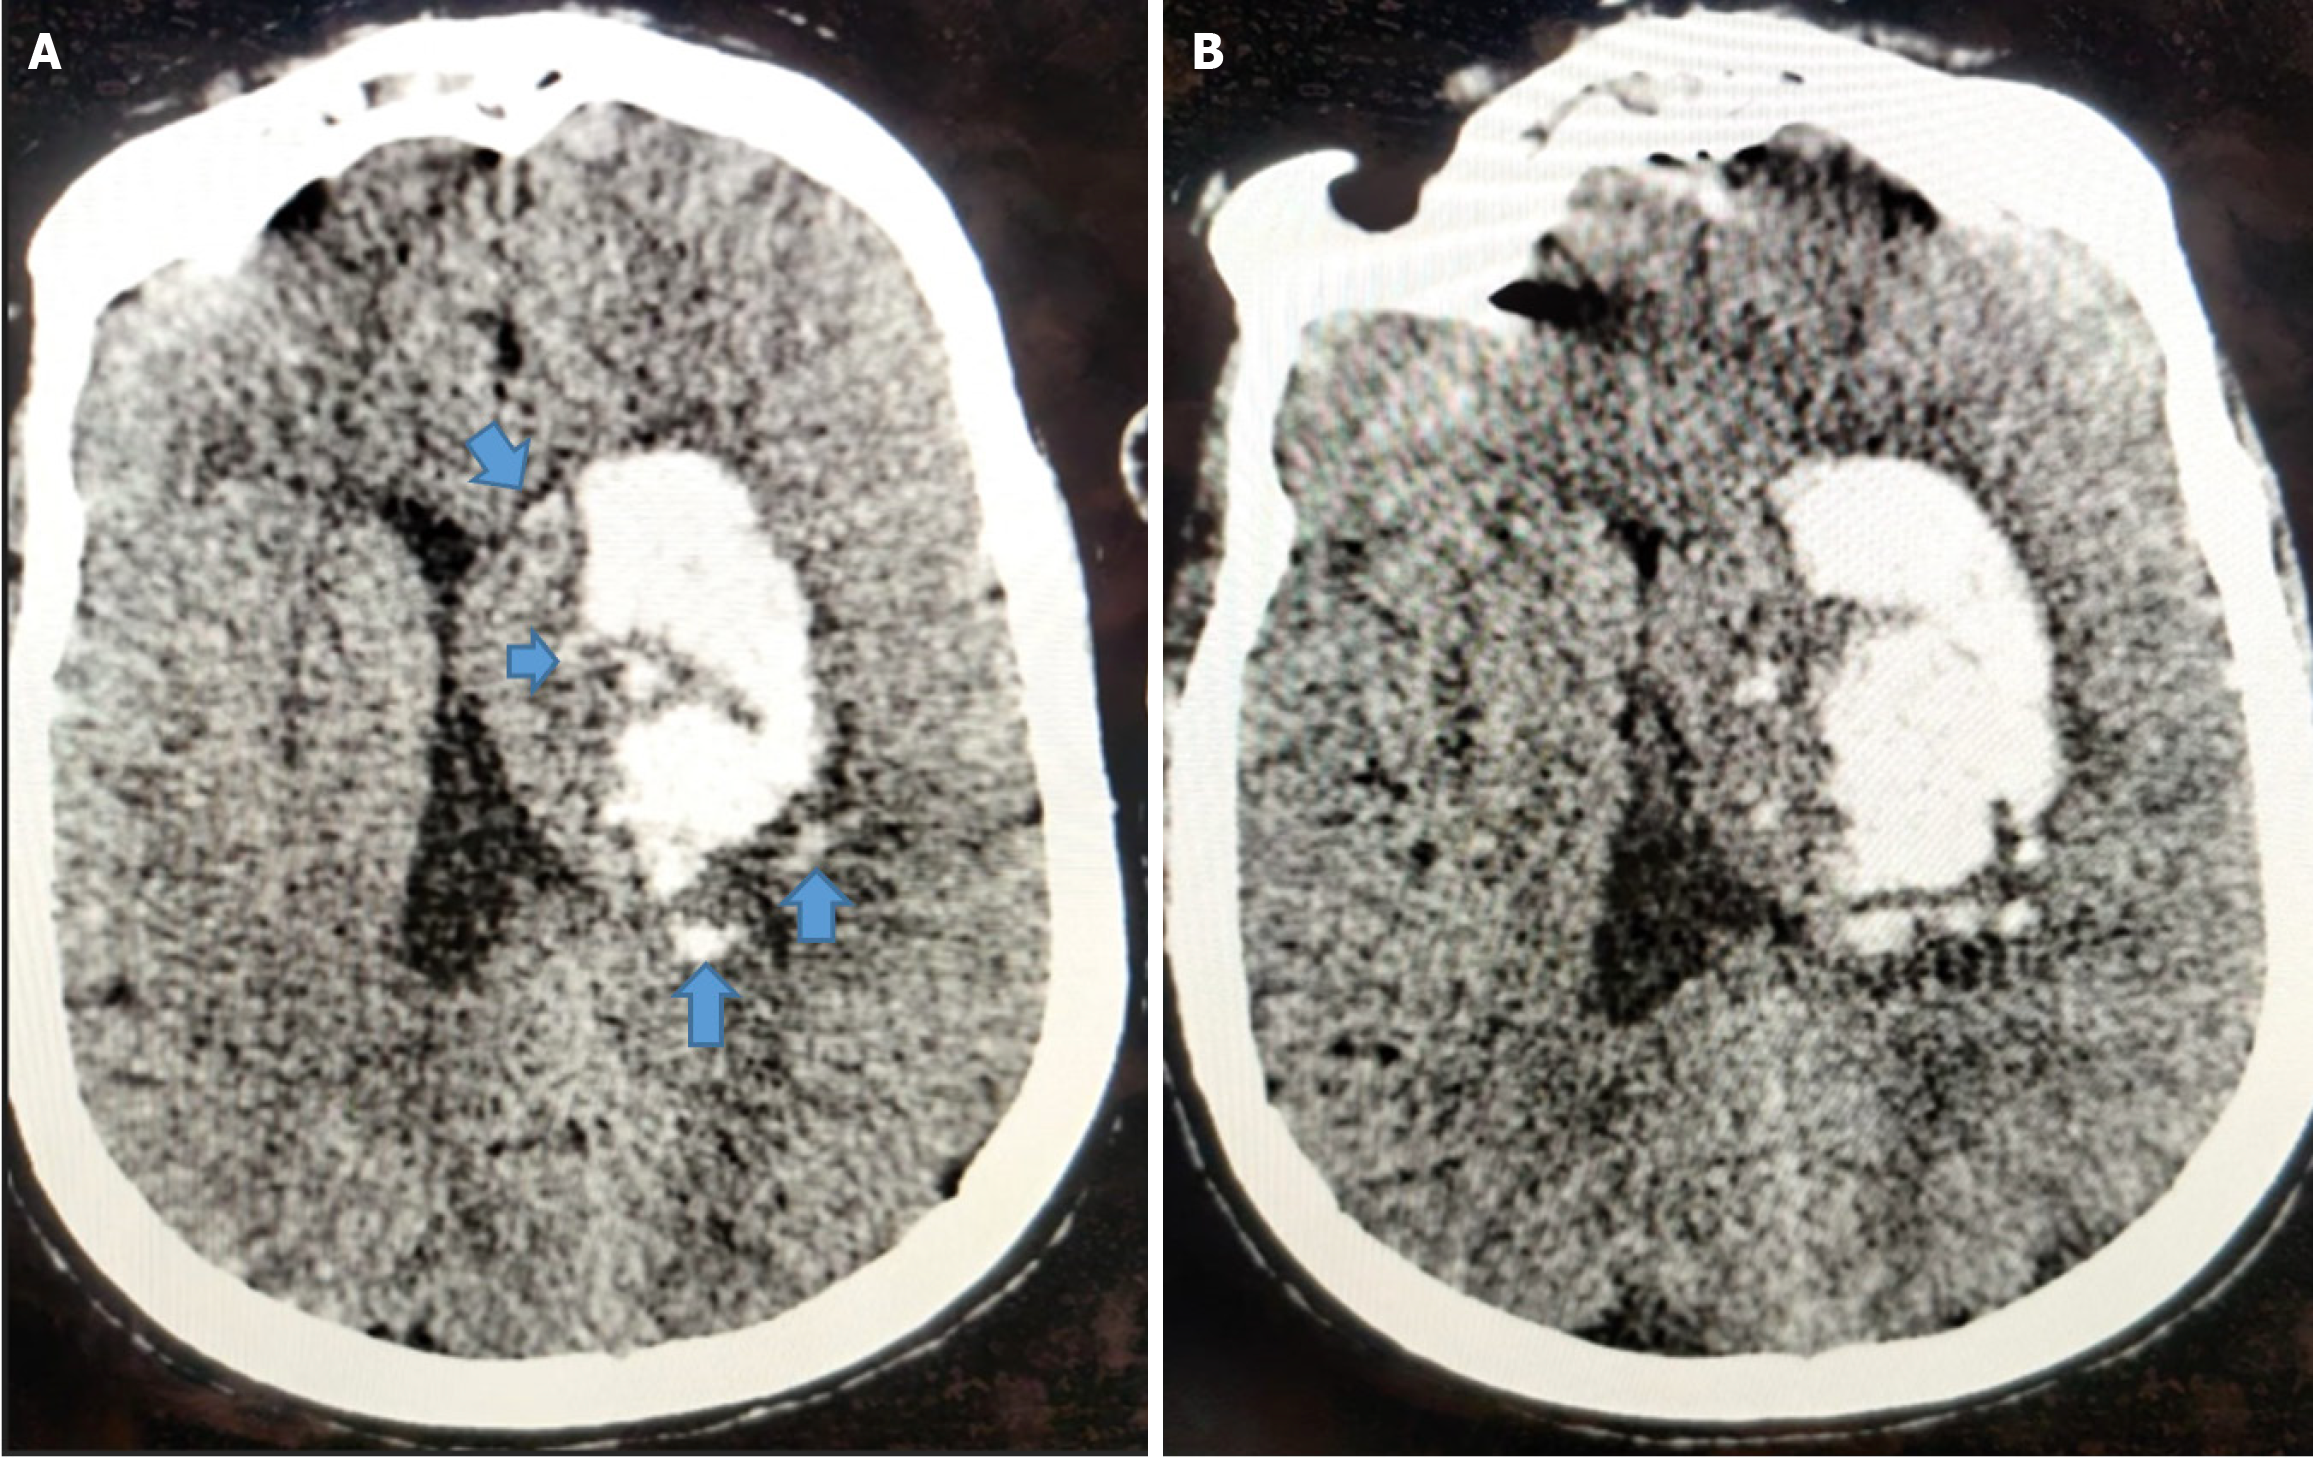

The island sign is defined as the presence of either three or more small, oval, or round hematomas separate from the main hemorrhage, or four or more sprout-like or bubble-like hematomas that may be connected to, but not lobulated with, the primary hematoma[21] (Figure 5).